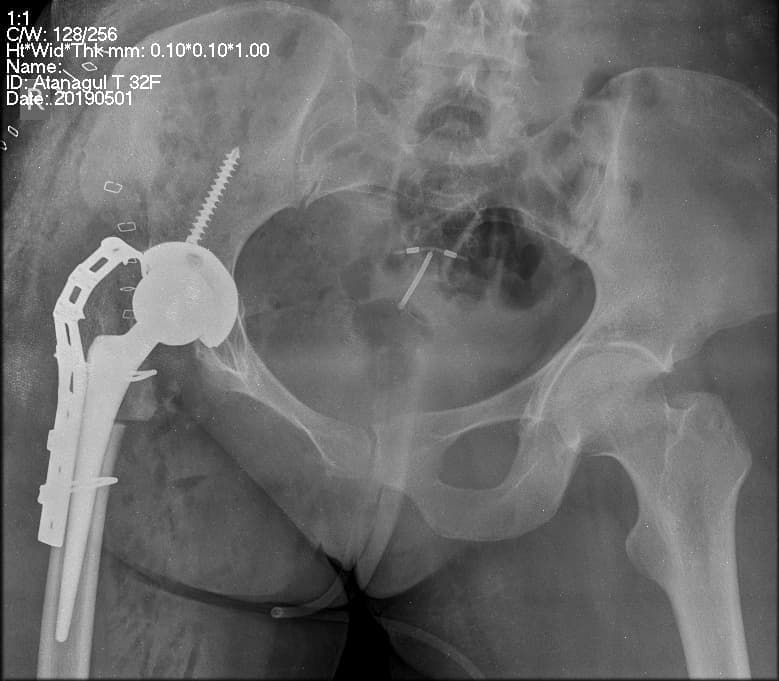

Түнхний толгой хэсгийн цусан хангамжийн алдагдалын улмаас үхжилт өөрчлөлттэй залуу өвчтөнд хүзүү хэсгийн богино шилбэний хиймэл үе суулгах мэс заслын өмнөх болон дараах рентген зураг

Түнхний үе бүтэн солих мэс засал (THA) image5Түнхний үе бүтэн солих мэс засал (THA) image6